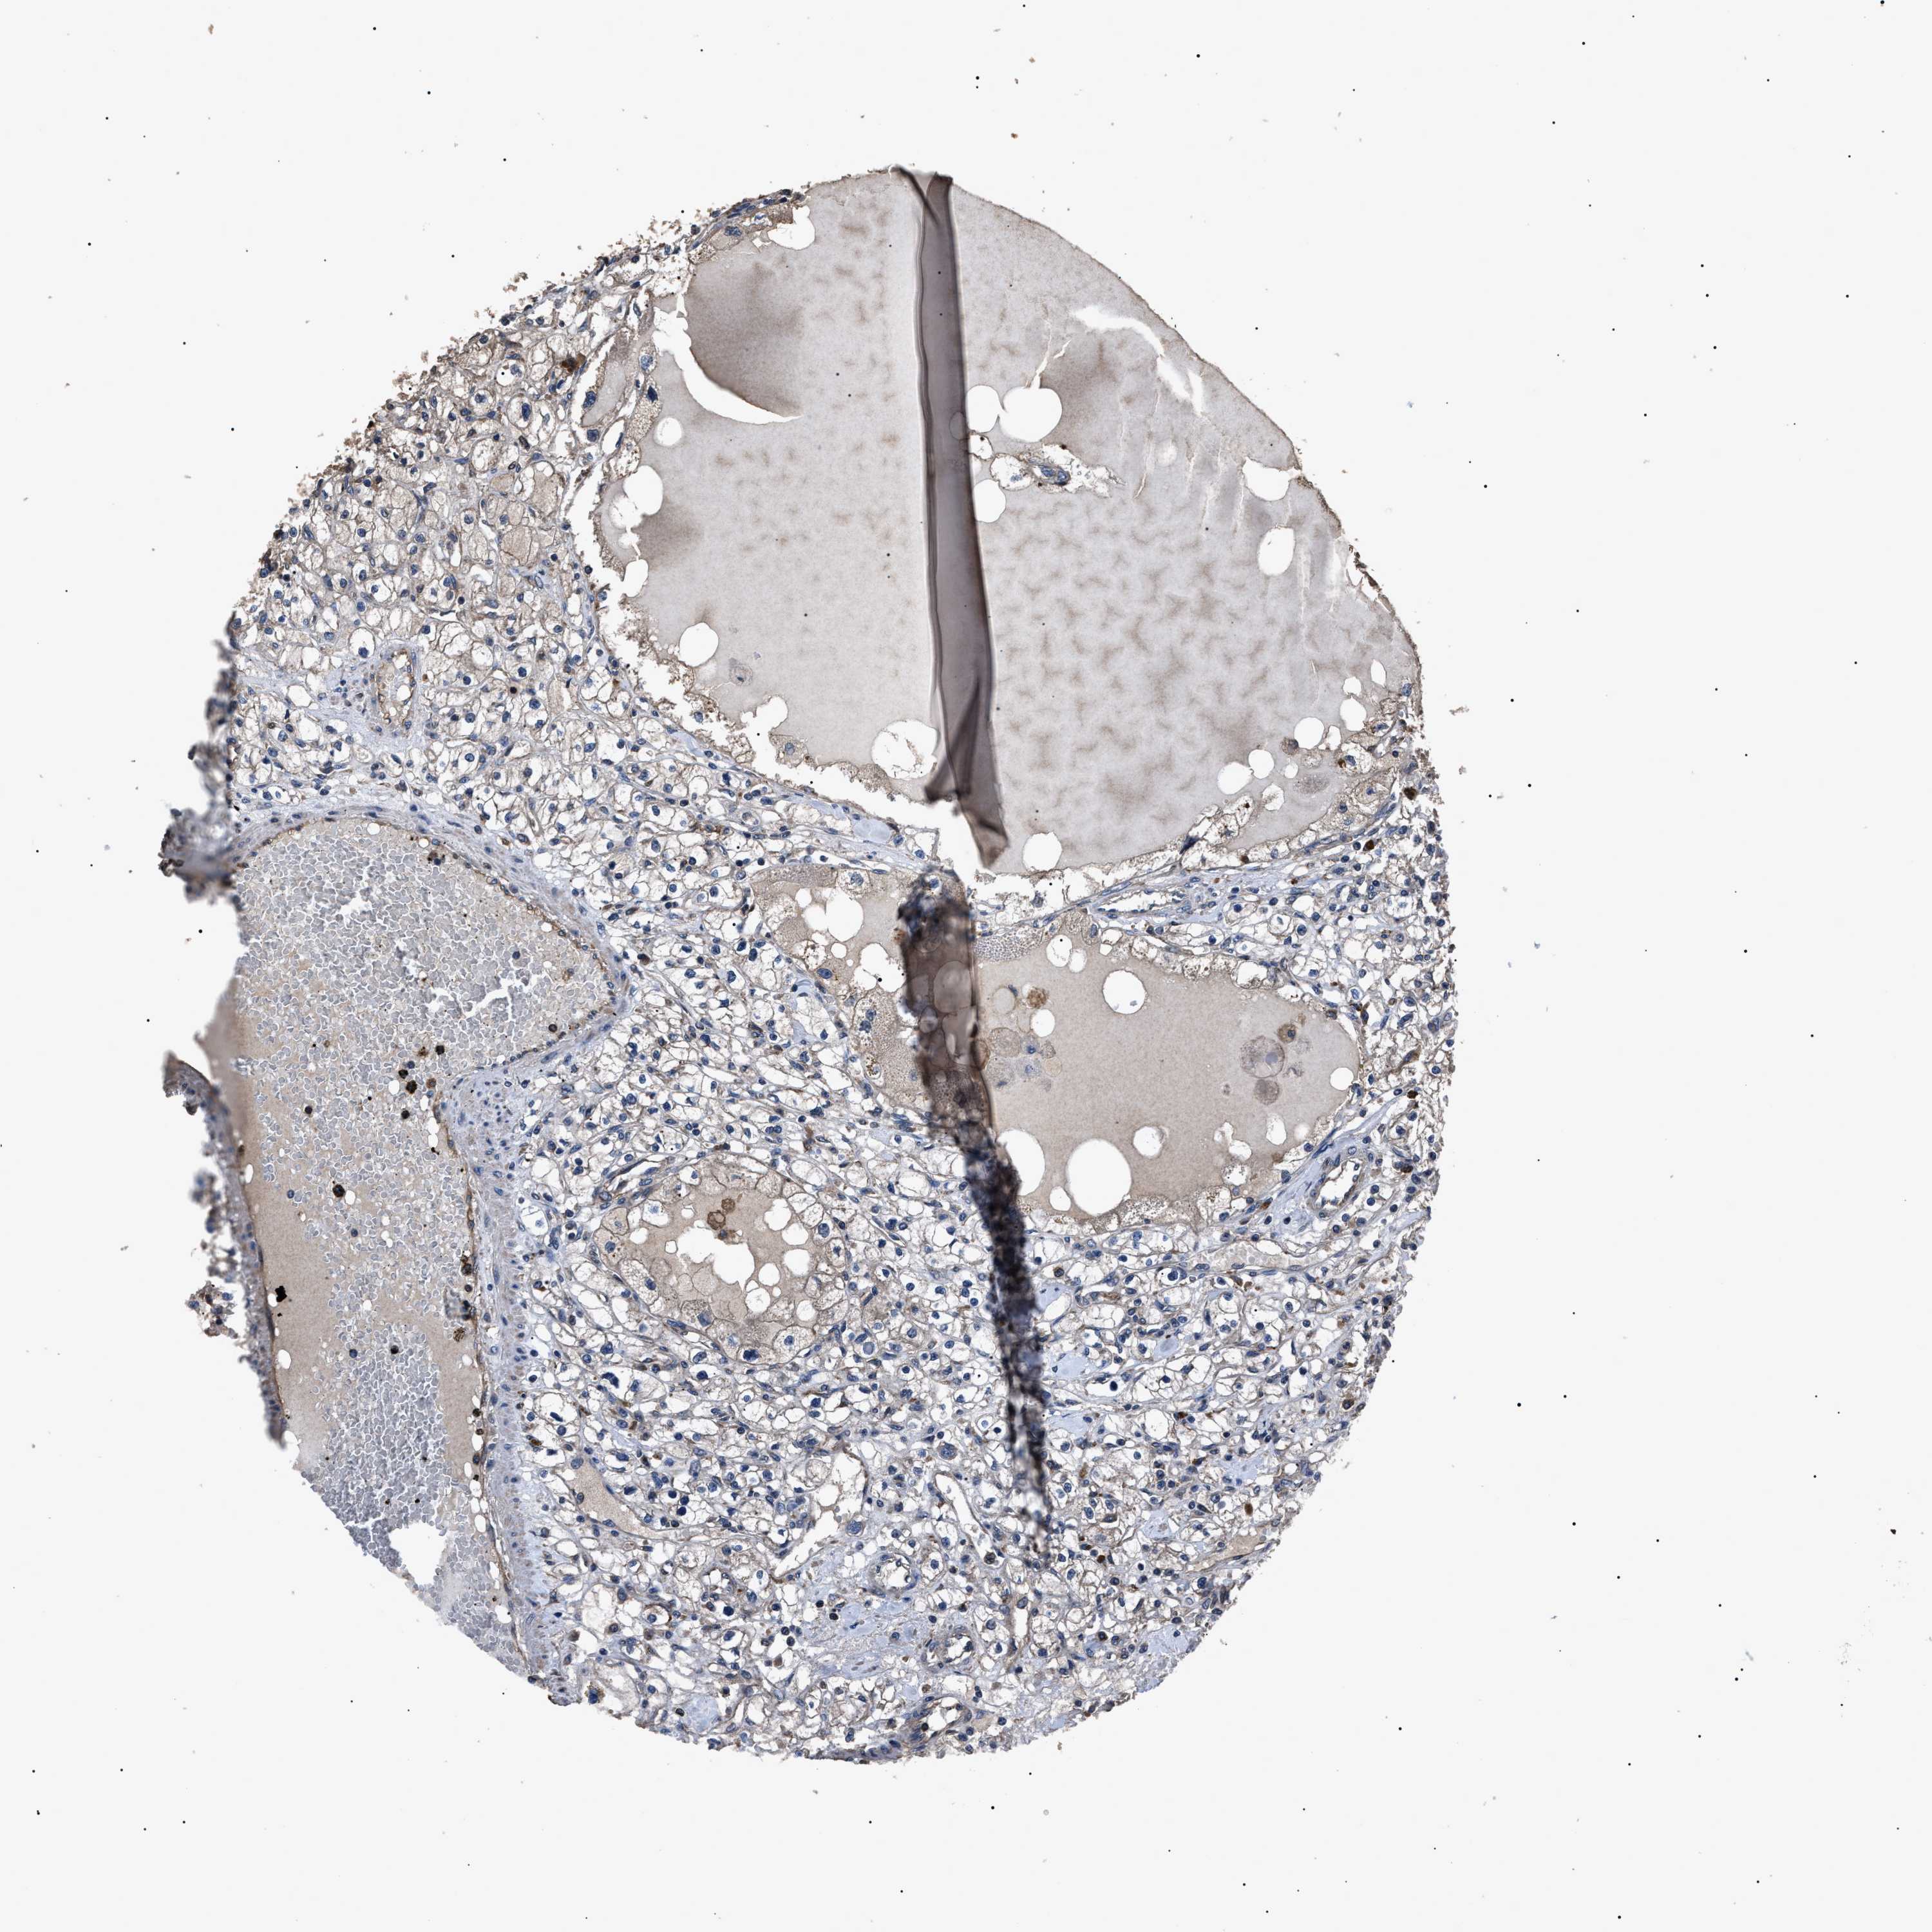

KIDNEY RENAL CLEAR CELL CARCINOMA (TCGA) - Interactive survival scatter ploti

The Survival Scatter plot shows the clinical status (i.e. dead or alive) for all individuals in the patient cohort, based on the same data that underlies the corresponding Kaplan-Meier plots. Patients that are alive at last time for follow-up are shown in blue and patients who have died during the study are shown in red.

The x-axis shows the expression levels (FPKM) of the investigated gene in the tumor tissue at the time of diagnosis. The y-axis shows the follow-up time after diagnosis (years). Both axes are complimented with kernel density curves demonstrating the data density over the axes. The top density plot shows the expression levels (FPKM) distribution among dead (red) and alive patients (blue). The right density plot shows the data density of the survived years of dead patients with high and low expression levels respectively, stratified using the cutoff indicated by the vertical dashed line through the Survival Scatter plot. This cutoff is automatically defined based on the FPKM cutoff that minimizes the p-score. The cutoff can be changed by dragging the vertical line or by entering a cutoff value in the square labeled "Current cut-off".

Under the Survival Scatter plot the p-score landscape (black curve; left axis) is shown together with dead median separation (red curve; right axis). Dead median separation is the difference in median mRNA expression between patients who have died with high and low expression, respectively. It is calculated as follows: median FPKM expression of dead patients with high expression - median FPKM expression of dead patients with low expression. This is intended to aid the user in visually exploring custom cutoffs and the associated p-scores and dead median separation.

Individual patient data is displayed and can be filtered by clicking on one or more of the category buttons on the top of the page. Categories describing expression level and patient information include: high, low, alive, dead, female, male and tumor stages. The scale of the x-axis can be toggled between linear and log-scale by clicking on the "x log" button. Mouse-over function shows TCGA ID, patient information and mRNA expression (FPKM) for each patient.

& Survival analysisi

Kaplan-Meier plots summarize results from analysis of correlation between mRNA expression level and patient survival. Patients were divided based on level of expression into one of the two groups "low" (under cut off) or "high" (over cut off). X-axis shows time for survival (years) and y-axis shows the probability of survival, where 1.0 corresponds to 100 percent.

RNF216 is not prognostic in Kidney Renal Clear Cell Carcinoma (TCGA)

Best expression cut offi

Based on the FPKM value of each gene, patients were classified into two groups and association between prognosis (survival) and gene expression (FPKM) was examined. The best expression cut-off refers the FPKM value that yields maximal difference with regard to survival between the two groups at the lowest log-rank P-value. Best expression cut-off was selected based on survival analysis .

When clicking on this number, the vertical dashed line indicating cut-off, the interactive survival plot, and the Kaplan-Meier curve will be adjusted to show results based on the best expression cut-off.

: 11.2

P scorei

Log-rank P value for Kaplan-Meier plot showing results from analysis of correlation between mRNA expression level and patient survival.

N/A

TCGA RNA samplesi

RNA-seq data is reported as average FPKM (number Fragments Per Kilobase of exon per Million reads), generated by the The Cancer Genome Atlas (TCGA) .

Normal distribution across the dataset is visualized with box plots, shown as median and 25th and 75th percentiles. Points are displayed as outliers if they are above or below 1.5 times the interquartile range. FPKM values of the individual samples are presented next to the box plot.

Average pTPM 13.0

Number of samples 521